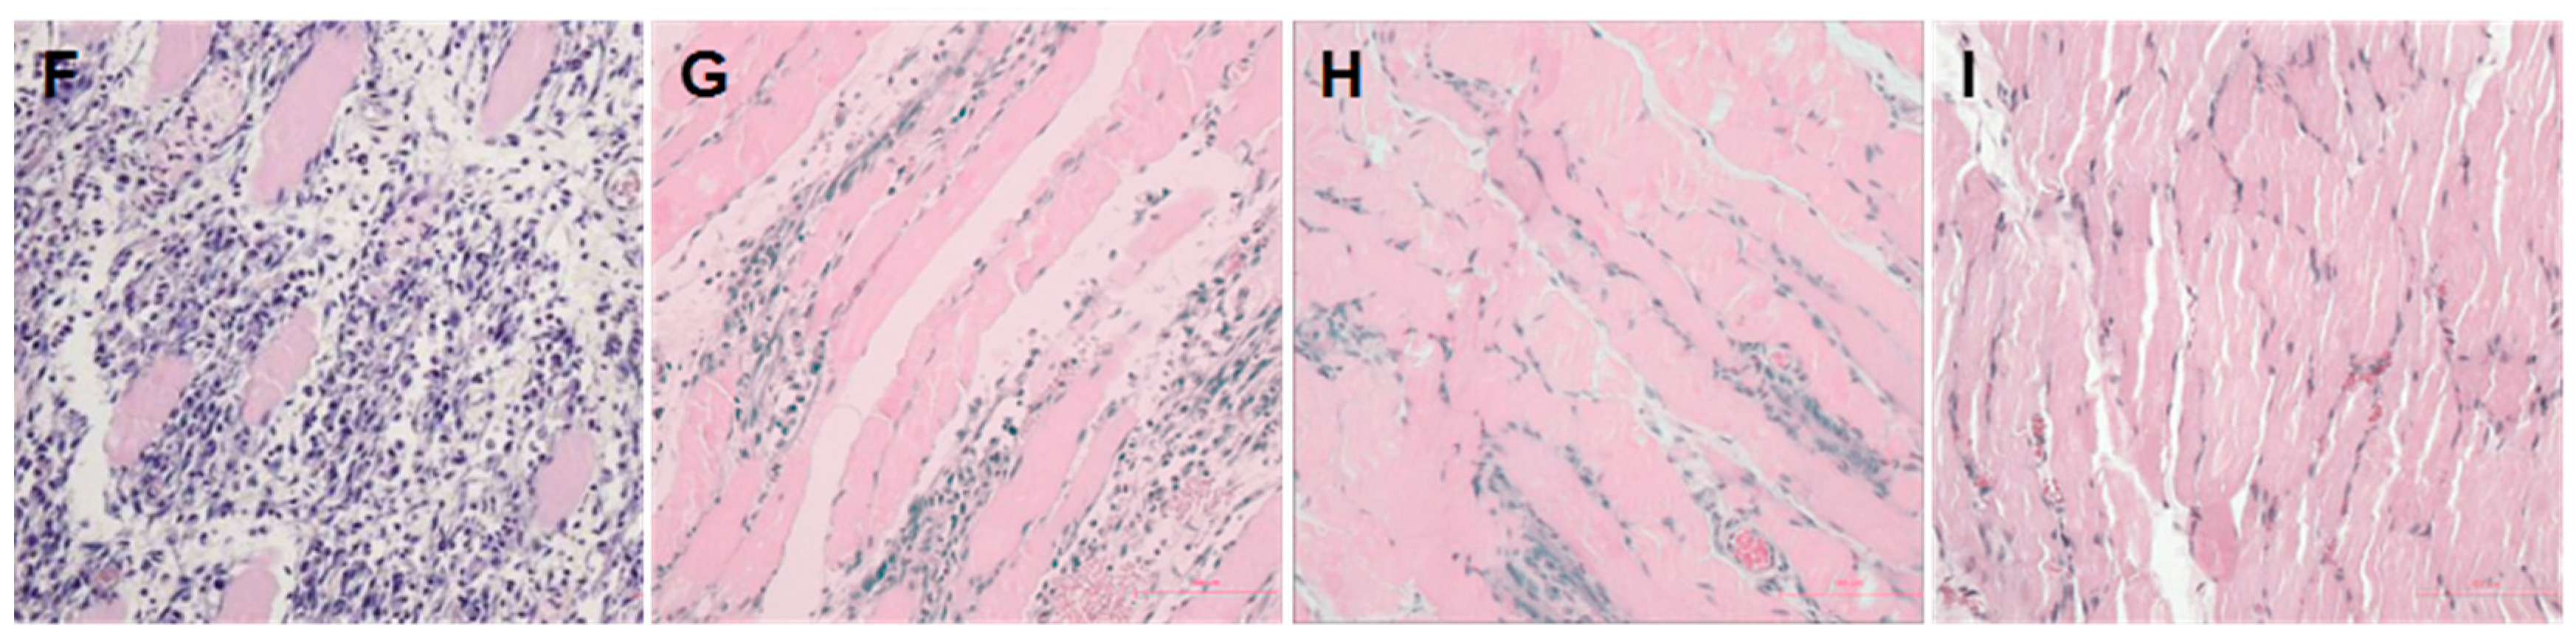

2.1. Establishment of a Pressure Ulcer Model

4.3. Histological Analysis